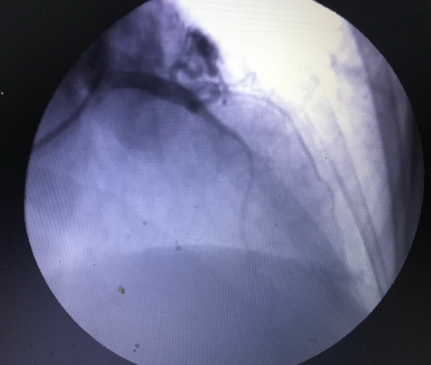

The authors present a 57-year-old woman with a left anterior descending to pulmonary artery fistula, causing progressive and daily ischemic chest pain associated with dyspnea and dizziness. Diagnosis was performed by coronary angiography and 3D computed tomography imaging reconstruction of the left anterior descending and pulmonary artery.

3D computed tomography imaging reconstruction of the LAD and PA and their insertion point to the PA are depicted.